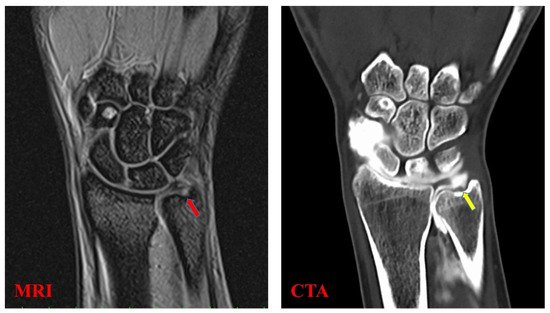

Motion Analysis of Triangular Fibrocartilage Complex by Using Ultrasonography Images: Preliminary Analysis

by Issei Shinohara, Atsuyuki Inui, Yutaka Mifune, Hanako Nishimoto, Kohei Yamaura, Shintaro Mukohara, Tomoya Yoshikawa, Tatsuo Kato, Takahiro Furukawa, Yuichi Hoshino, Takehiko Matsushita and Ryosuke Kuroda

Sensors 2022, 22(1), 345; https://doi.org/10.3390/s22010345 - 4 Jan 2022

The triangular fibrocartilage complex (TFCC) is a significant stabilizer of the distal radioulnar joint. Diagnosing TFCC injury is currently difficult, but ultrasonography (US) has emerged as a low-cost, minimally invasive diagnostic tool. We aimed to quantitatively analyze TFCC by performing motion analysis by [...] Read more.

The triangular fibrocartilage complex (TFCC) is a significant stabilizer of the distal radioulnar joint. Diagnosing TFCC injury is currently difficult, but ultrasonography (US) has emerged as a low-cost, minimally invasive diagnostic tool. We aimed to quantitatively analyze TFCC by performing motion analysis by using US. Twelve healthy volunteers, comprising 24 wrists (control group), and 15 patients with TFCC Palmer type 1B injuries (injury group) participated. The US transducer was positioned between the ulnar styloid process and triquetrum and was tilted ulnarly 30° from the vertical line. The wrist was then actively moved from 10° of radial deviation to 20° of ulnar deviation in a 60-rounds-per-minute rhythm that was paced by a metronome. The articular disc displacement velocity magnitude was analyzed by using particle image velocimetry fluid measurement software. The mean area of the articular discs was larger on ulnar deviation in the control group. The mean articular disc area on radial deviation was larger in the injury group. The average articular disc velocity magnitude for the injury group was significantly higher than that for the control group. The results suggest that patients with TFCC injury lose articular disc cushioning and static stability, and subsequent abnormal motion can be analyzed by using US. Full article